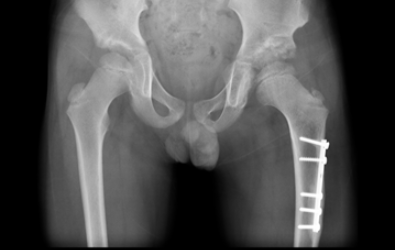

The x-rays show cases of developmental dysplasia of the in the hips that presented after the age of three years. The patients underwent surgery by Dr. Zenios for hip reduction with a pelvic and femoral osteotomy.

Pre-operative

Post-operative